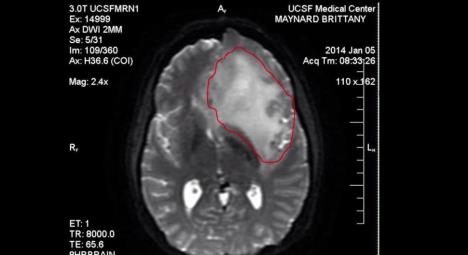

Mejnardovoj je u aprilu dijagnostikovan agresivan oblik tumora na mozgu. Lekari su joj tada davali još šest meseci života, a ona se u Oregon, jednu od pet američkih država koja dozvoljava medicinski potpomognuto samoubistvo, prenosi piše Njujork dejli njuz.

"Danas je dan kada sam odlučila dostojanstveno da umrem zbog svoje smrtonosne bolesti... tog strašnog raka na mozgu, koji mi je mnogo toga oduzeo, ali oduzeo bi mi još i više".